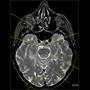

MRI of

horizontal section in

human